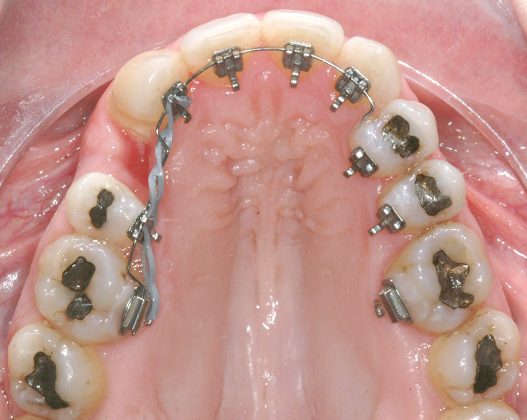

Il protocollo terapeutico ha previsto l’estrazione del primo premolare inferiore sinistro (3.4) e del primo superiore destro (1.4), l’applicazione di una apparecchiatura fissa linguale 2D e di una meccanica asimmetrica di ancoraggio e movimento ortodontico a entrambe le arcate (Figure 3a-b).

Il trattamento è iniziato con l’estrazione dei due premolari in unica seduta in anestesia locale e l’applicazione simultanea, dopo una settimana, della apparecchiatura linguale inferiore e superiore, non essendoci problemi di overbite e potenziali interferenze in occlusione tra l’apparecchiatura superiore e i frontali inferiori. All’arcata superiore è stata effettuata una iniziale chiusura dello spazio estrattivo con forze molto leggere in ancoraggio medio su arco .014” Nichel-Titanio e successivamente .016” Nichel-Titanio, bondato in prima fase per maggior stabilità direttamente sulla superficie mesiale di 2.4.

Nota tecnica: il movimento iniziale di distalizzazione della corona di 1.3 mediante tipping distale (vista la posizione radicolare iniziale) è stato ottenuto con una catenella elastica leggera inserita su 1.6, 1.5 e ancorata su 1.3, abbracciando per maggior controllo l’aletta disto-occlusale e quella gengivale del bracket linguale.

Per la chiusura dello spazio all’arcata inferiore, dopo la preliminare fase di allineamento e livellamento2, con la stessa sequenza iniziale di archi (.014” e poi .016” Nichel-Titanio), è stato temporaneamente applicato un sistema di ancoraggio ausiliario vestibolare, mediante fibre rinforzate, bondate sulla superficie vestibolare di 3.5, 3.6, 3.7 (Figura 4).